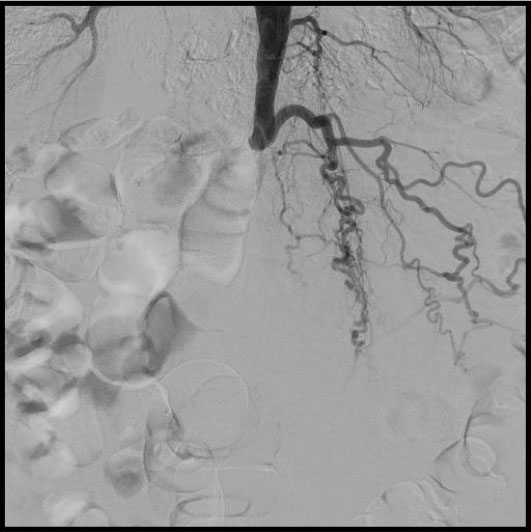

По рекомендации знакомых пациент обратился в клинику ЦЭЛТ, где выполнено УЗИ, компьютерная томография и ангиография брюшного отдела аорты и артерий нижних конечностей.

В ходе обследований было выявлено критическое поражение сосудов – ниже отхождения почечных артерий полная окклюзия (закупорка) брюшного отдела аорты, левой и правой подвздошных артерий. Кровоток к бедренным артериям и ниже доходил в недостаточном количестве, через обходные сосуды (коллатерали).